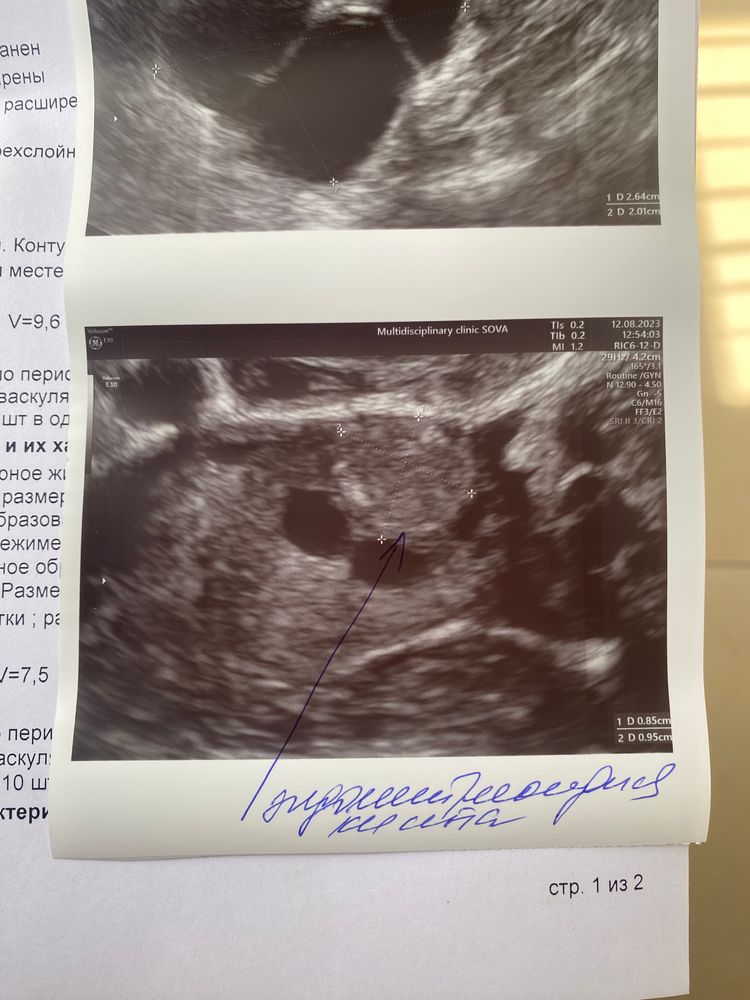

Дашуля, вот буду консультироваться с разными гинекологами что с ней делать.. Изображение